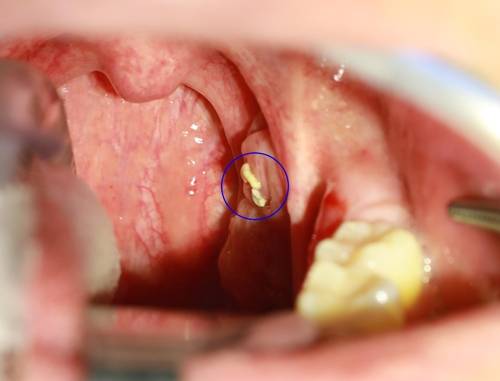

입안을 보면 목젖 양쪽에 볼록한 편도가 있다. 편도의 표면에는 '편도와'라는 작은 구멍이 있는데 여기에 생기는 노란 이물질을 편도결석이라고 한다.

편도결석은 정상적으로 생기는 편도 분비물이 입안의 음식물, 세균 등과 반응하면서 생긴 노란색의 덩어리를 말한다. 이를 편도에 생기는 돌이라고 해서 편도결석이라고 부른다.

하지만 실제로 만져보면 딱딱하지는 않고 치즈와 같은 느낌을 준다. 편도결석의 크기는 쌀알 크기 정도부터 어른 손톱만 한 것까지 다양하다. 편도결석이 있으면 입 냄새가 심하고 목에 뭐가 있는 듯한 이물감이 주로 나타난다.

![편도결석(파란색 원 부분) [하나이비인후과병원 제공]](https://img2.daumcdn.net/thumb/R658x0.q70/?fname=https://t1.daumcdn.net/news/201903/23/yonhap/20190323080009058nnji.jpg)